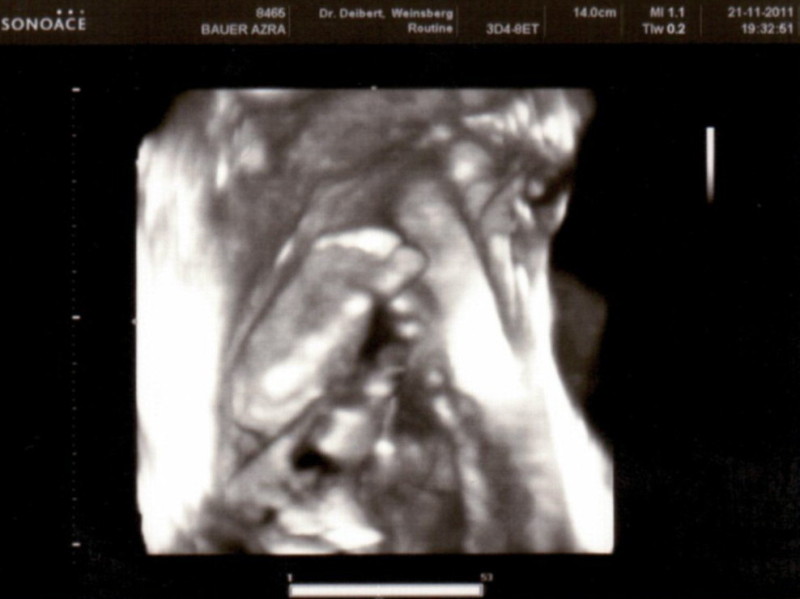

Sono-Pics vom Junior

Auch wenn er sich nicht gerne fotografieren läßt (ganz die Mama) haben wir doch ein paar Schnappschüsse von ihm.